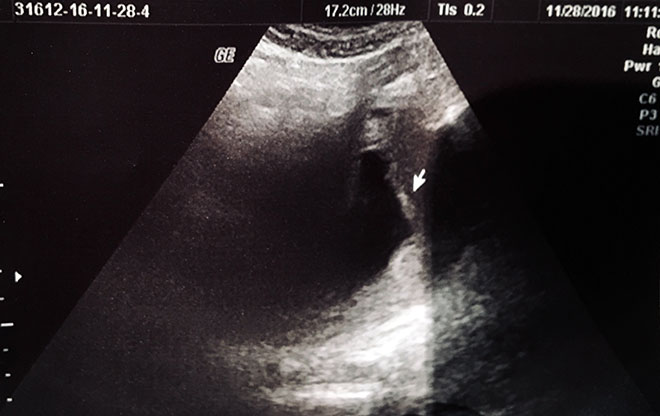

УЗИ диагностика

Только на шестой неделе беременности пустое плодное яйцо можно диагностировать с помощью УЗИ. Оно проводится в любом случае, чтобы определить месторасположение плода, а также исключить внематочную беременность. Такой страшный диагноз, как анэмбриония женщина может услышать даже если чувствует себя хорошо и у нее нет никаких симптомов. Первый триместр беременности это наиболее важное время формирования плода, на данном этапе будущей маме стоит особо тщательно следить за своим здоровьем, так как угроза выкидыша очень высока.

В этом видео показано УЗИ пустого плодного яйца:

При завершении любого из двух методов аборта нужно сделать УЗИ. Таким образом, можно удостовериться, что матка чистая и в ней не остались частички плодного яйца.